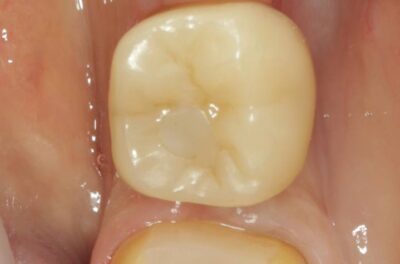

Протезирование коронками из диоксида циркония, после эндодонтического лечения — Исламов Л.А.(01.04.2026)